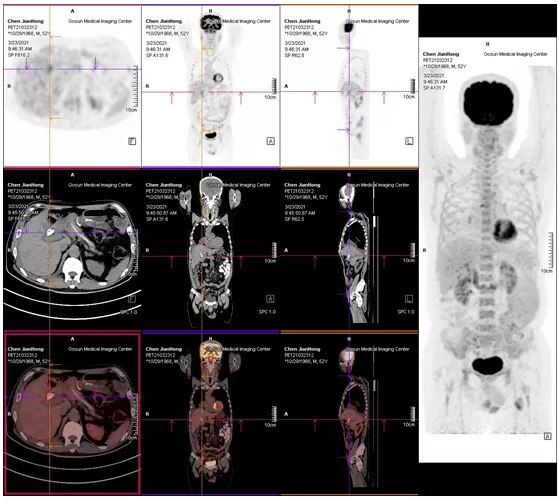

06

2021年05月 PET/CT檢查結果

復查PET-CT提示原術區(qū)復發(fā)病灶、肝內轉移灶、右側胸膜轉移灶控制良好

image.png

治療效果評估

用藥3個月后,患者精神狀態(tài)明顯好轉,食欲改善,體重增加,腫瘤指標下降,PET/CT結果提示,無明顯腫瘤復發(fā)或轉移征象,肝內腫瘤活性已受抑制。